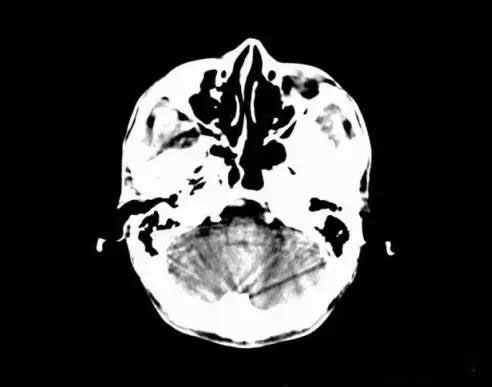

5、部分容積效應(yīng)產(chǎn)生的偽影及對策

部分容積效應(yīng)偽影的形狀可因物體的不同而不一樣,一般在重建后橫斷面圖像上可見條形、環(huán)形或大片干擾的偽像。最常見和典型的現(xiàn)象是在頭顱橫斷面時的顳部出現(xiàn)的條狀偽影,又稱哼氏偽影。該偽影現(xiàn)象可采用薄層掃描而減弱;在西門子系列的CT機中.用VAR掃描技術(shù)可抑制該偽影。